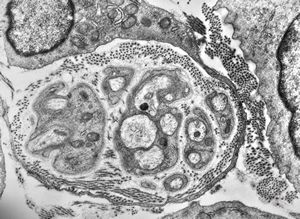

M, 3y. | cutaneous nerve

M, 62y. | mitosis … angiomatous tumor, v.s. Kaposi sarcoma

M, 62y. | angiomatous tumor, v.s. Kaposi sarcoma

M, 62y. | Weibel-Palade body - angiomatous tumor, v.s. Kaposi sarcoma